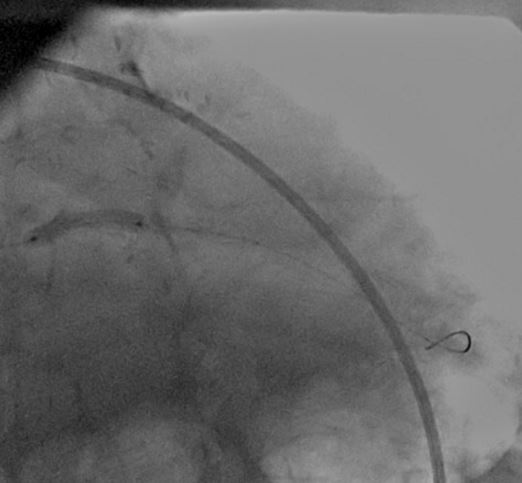

A CLs guiding catheter was used to engage the left coronary artery, and a Choicd floppy guidewire passed through the lesion. The lesion was predilated with a 1.5x15mm and 2x10mm Maveric balloon (figure 4). Then a 3.5x18mm Xience v stent was deployed at 16atm (figure 5, figure 6, figure 7). Post-dilation was done with a 4x10mm Firestar NC balloon (figure 8). The final result showed TIMI-III flow with no residual stenosis (figure 9).